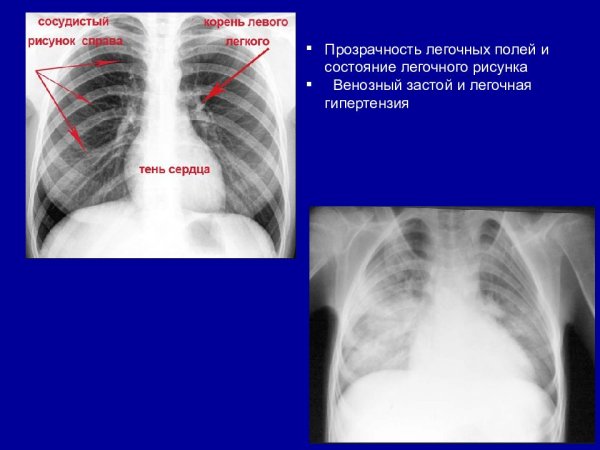

Синдром обогащения легочного рисунка рентген